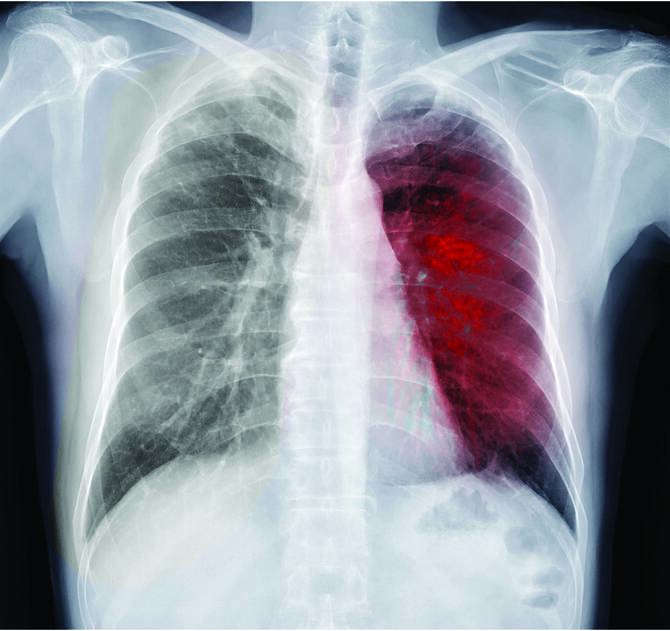

Chest X-ray of human chest or lung to detect tuberculosis. (Getty Images)